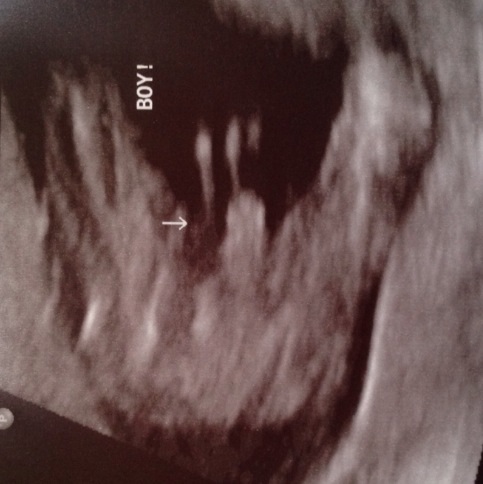

I just moved to Japan and today I had my a/s. I asked my doctor for the gender if he could get a good shot. He gave me the ultrasound prints but didn't actually tell me the gender. When I asked, he just pointed to the print outs. So, can you ladies help me? I think it's a boy, but I want others who may actually know what to look at.

EDIT TO UPDATE: It's a boy!!! My doctor said he couldn't get a perfect shot of the potty parts, but he's pretty certain it's a boy. He also told me that his office does an ultrasound at every appointment and he can recheck at my next appointment to be completely sure.

Here is a boy view for comparison: